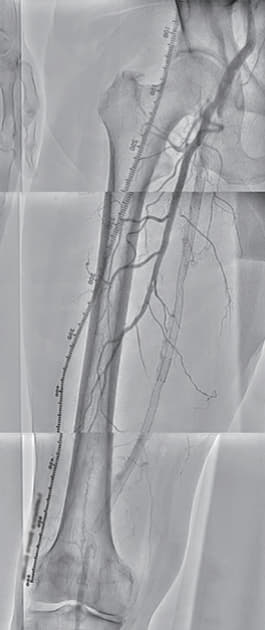

7年ぶりに跛行が再燃し、数か月間の薬物運動療法を経てなお症状が改善しない。造影を行うと過去に右浅大腿動脈(SFA)に留置された総長約35 cmのベアメタルステント(BMS)の入口部から閉塞していた。ステント内を大量の器質化血栓が占めており、バルーンベースでの治療では良好な仕上がりは得られないため、バイアバーン® ステントグラフトを2本、ステントをフルカバーして留置した。

過去にSFAに留置された総長約35 cmの3本のBMSの入口部からの閉塞(動画1)近位端はSFA入口部から1 cm程度の健常部があり、遠位端は膝窩動脈近位部(P1)で側副血行流入部まで1 cmの余白がある。対側山越えアプローチで6 Frガイディングシースを挿入して治療を開始した。ステント外を通過しないように0.035 inchのガイドワイヤーを選択すると容易に遠位部へ到達することが出来た(動画2)。この手ごたえから血栓性病変であることが予想された。持続吸引カテーテルを用いて何度か血栓吸引を行ったが血流は再開しなかった(動画3)。

血管内超音波(IVUS)を行うとガイドワイヤーはステントの中心部を通過していたが、予想通り病変内には大量の血栓が堆積していた(動画4)。7 mmのバルーンで拡張したのち、ステント遠位端より2 cm程度離れた遠位の健常部にhealthy landingをとって(動画5)バイアバーン® ステントグラフト6 × 250 mmを留置した。近位側はステント近位端より1 cm程度離れたSFA入口部の健常部にhealthy landingをとって(動画6)バイアバーン® ステントグラフト7 × 150 mmを留置した。上下端とも既存のステントより外側にランディングをとること、ステントグラフトの電子添文の「使用上の注意」にあたる主要な側枝に注意して、大腿深動脈(DFA)や側副血行の流入部にかからないよう留意した。後拡張は血栓の上下方向へのprotrusionを防ぐ目的で先に遠位端、近位端の順に高圧バルーンで拡張し健常部血管壁への圧着をとった。ステントグラフトの中間部への後拡張はそのあとに続いて行った。最終造影で末梢まで塞栓がないことを確認して終了した(動画7)。